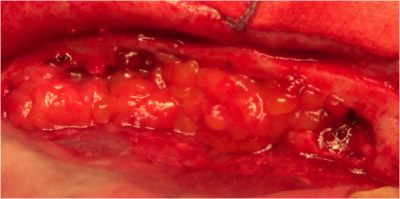

8. The first time was FESS. We proceeded to interruption of the synechiae at level of nasal-frontal duct to reach the region of the mucus-piocele that overlooked the left orbit (Figure 4).

9. So it was facilitated the drainage of mucus-pus nasally by the help of the second operator who performed repeated maneuvers of eye’s pressure (Figure 5).

Figure 4 Left synechia at level of nasal-frontal duct.

Figure 5 Nasally drainage of mucus-pus.